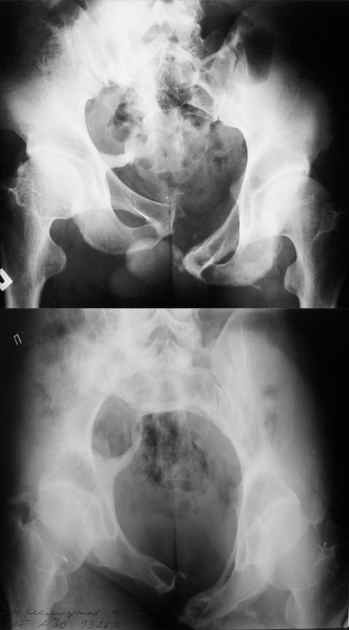

Маленькая иллюстрация (около 5 лет после травмы). Результат плохой - укорочение, хромота, периодически боли в спине, но больной отказывается от операции, видимо, не так все трагично.